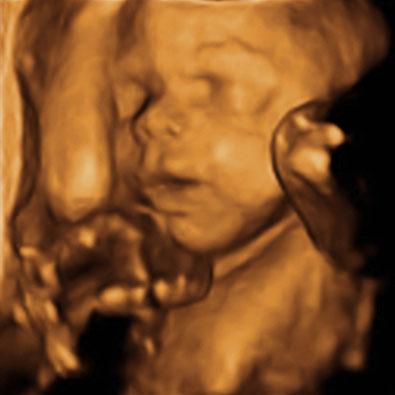

Hier unser 3D-Bild! Mein Mann und ich haben schon festgestellt, das sie die gleiche Nase hat wie ihr großer Bruder. Nur der Mund ist größer ;-)

oooh wie hüüübsch!!! Ein tolles Bild!! Find das toll wie viel man da schon erkennen kann und auch Ähnlichkeiten, wie Du sagst... usw.! Wahnsinn...

Wow ist das ein gelungenes 3D Bild von eurer Prinzessin, da kommt man glatt ins schwärmen... Hoffe das man bei uns das auch sooooo schön sehen kann.

Wow das Foto ist echt super. Unsere versteckt sich immer, konnte ihr Gesicht nie wirklich sehn. Und das wichtigste aber ist,dass alles in Ordnung ist. Da fällt einem schon mal ein rießen Stein vom Herzen. Lg

Glückwunsch zur Prinzessin! Toll dass Alles ok ist mit der Kleinen! Das 3D-Bild ist wunderschön, sowas hätte ich auch gerne, das dauert aber noch so 2-3 Wochen da ist Termin ... hoffe sie zeigt sich dann auch so toll, wie Dein Mädel :-))! LG Mone